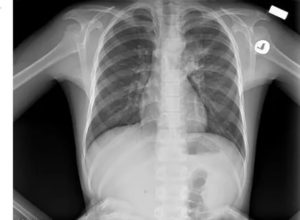

Детская рентгенография при вирусной или пневмоцистной пневмонии отличается от взрослой. Делать снимок и расшифровывать его необходимо как можно скорее, поскольку даже мелкие воспаления быстро разрастаются, проводя к крупозной форме, затрагивающей оба лёгких.

Рентгенологическая картина у детей выглядит так:

- небольшие, 1-2 мм, локальные потемнения в нижней части лёгких;

- плотные пятна при глубоком воспалении;

- увеличение лимфоузлов средних отделов грудной клетки не отображается на снимке;

- нарушения рисунка после исчезновения теней сохраняются ещё неделю;

- плотные участки воспаления перекрывают лёгочный рисунок.

У детей часто наблюдается вздутие тканей лёгких. Это затрудняет рентгенодиагностику, которая не покажет некоторые разновидности болезни.

Особую опасность представляет пневмония, поразившая легкие ребёнка. Такое заболевание вылечить сложнее всего, но если вовремя сделать рентген и следовать рекомендациям врача, то опасности для жизни болезнь всё же не представляет. Вот основные признаки, которые наблюдаются на рентгене при пневмонии у детей:

- наличие небольших теней очагового характера;

- значительное увеличение плотности любых затемнений, когда заболевание только прогрессирует;

- значительное увеличение и уплотнение лимфатических узлов, расположенных неподалеку;

- значительное усиление и деформация сосудистого рисунка лёгких;

- существенные изменения корня легкого на той стороне, которая была подвержена пневмонии (изменения связаны и с размерами и со структурой).

Характерной особенностью этого заболевания у детей является то, что изменения на рентгеновских снимках наблюдаются на протяжении длительного времени даже после клинического выздоровления.